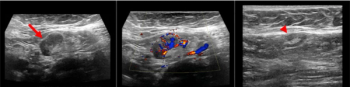

Swollen lymph nodes visualized on mammography and ultrasound appear days post-vaccination and could be mistaken for malignancies.